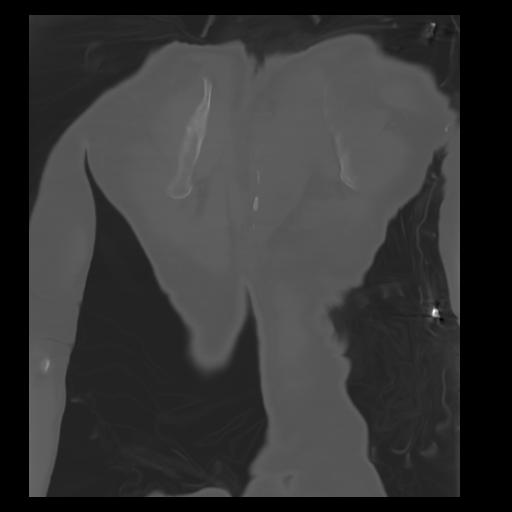

29 CUERPO,CE,Coronal,3.000,CUERPO,Coronal,